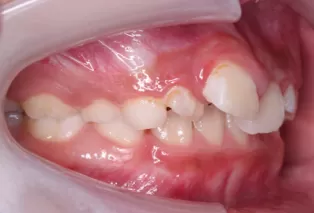

Intraoral photos